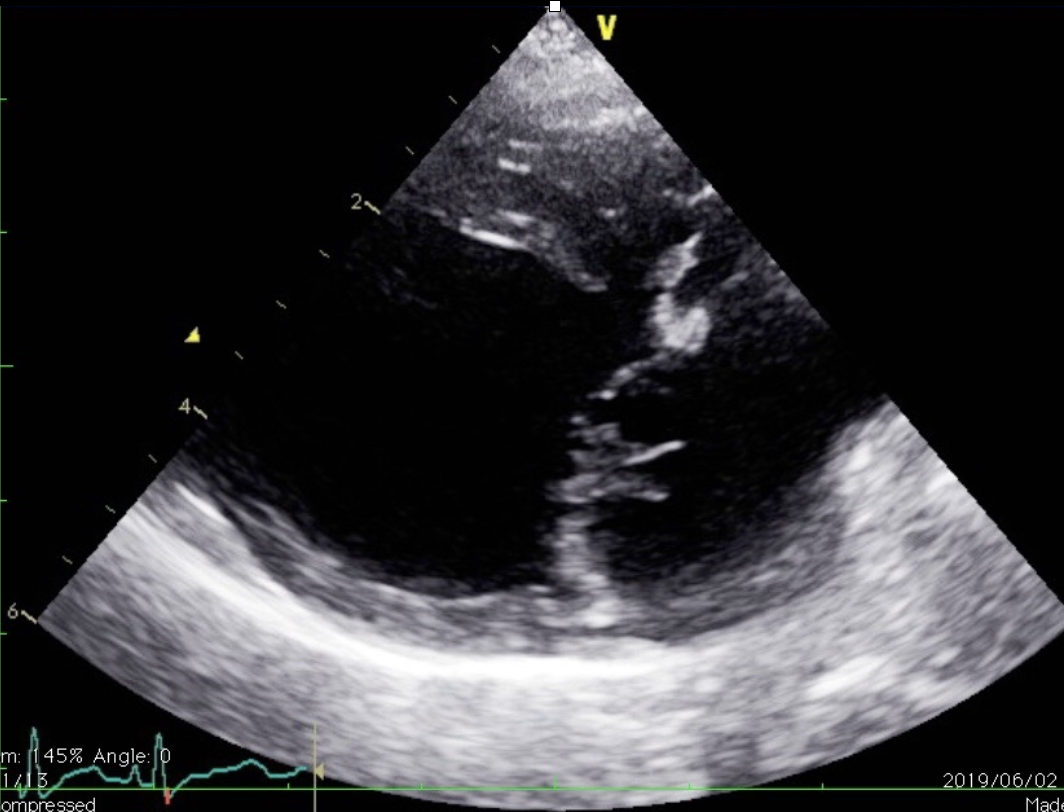

僧帽弁閉鎖不全では、弁の腱索という紐状の部分が断裂し、急激な悪化を示す場合が多く、肺水腫を呈している症例の大部分は腱索断裂を起こしております。また心臓は逆流により拡大しているため、弁と弁の間が拡張し広がっているため、弁が接合する面積が減少しておりより逆流しやすい状況となっています。

心臓の手術では、この腱索した断裂を修復する腱索再建術と、広がった心臓の弁の周辺を糸を使って縫い縮める弁輪縫縮術の二つを組み合わせて治療を行っています。

腱索再検手術は、千切れた腱索をゴアテックスという糸を使用して、弁の修復を実施します。

弁輪縫縮手術は、心不全により拡大してしまった心臓の弁の付け根(弁輪)を、縫縮めることで元に近い位置に戻してあげる手術になります。